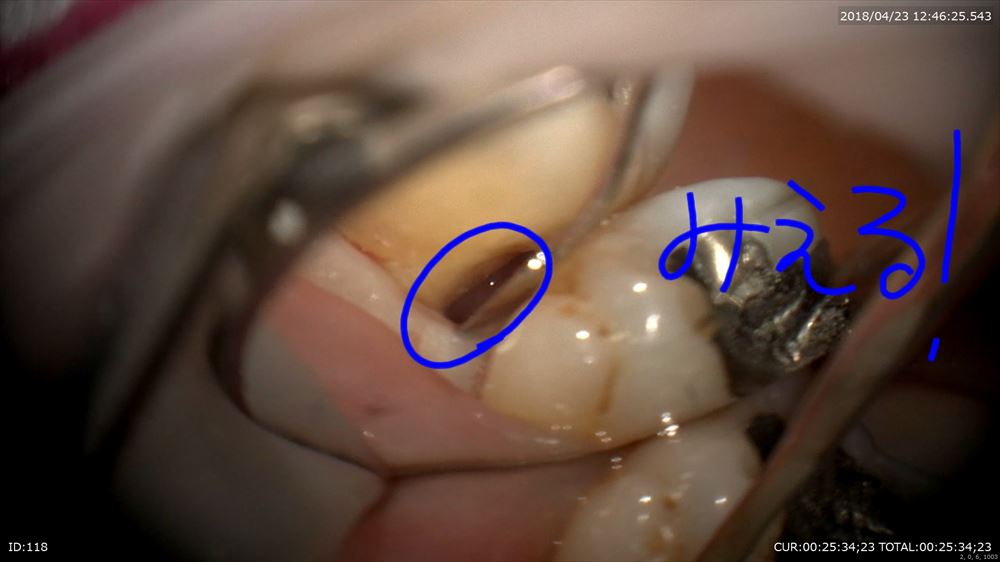

マイクロスコープでポケットの中の歯石(細菌)をみて

秋山勝彦先生ご発明の器具で剥離

この様に歯茎を切らずに歯肉溝からのアプローチ。この器具ミラーの役割もします。

歯根形態がこのように見えるからデブライドメントも、「なんとなく」ではなく歯根にきちっと合わせて行えます。